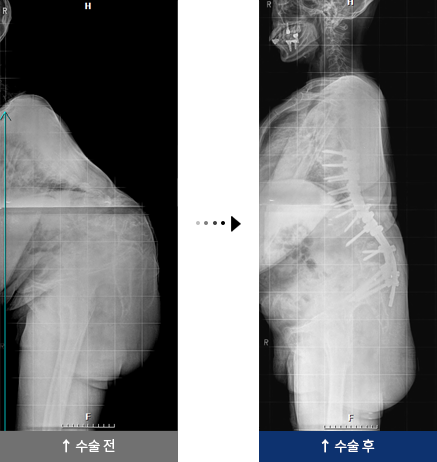

결핵성 후만증